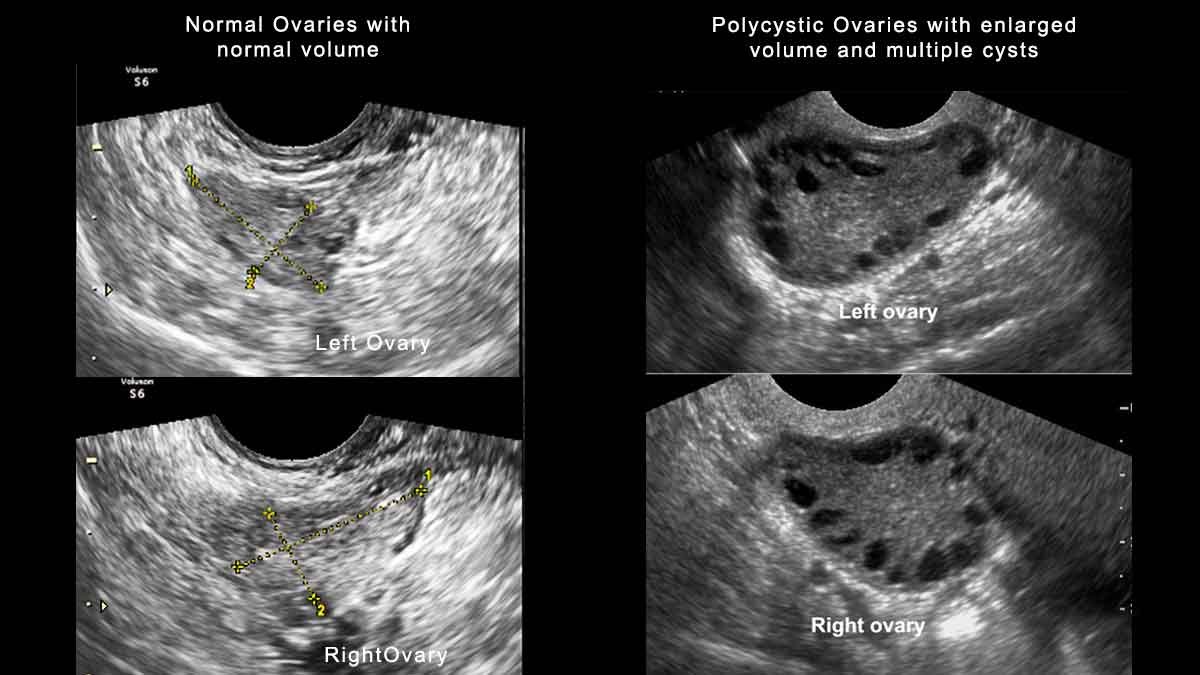

Діагностика — не з легких. Вона вимагає ультразвукового дослідження, аналізу гормонів та інших обстежень. Іноді процес нагадує детективний фільм, де треба зібрати всі шматочки пазлу, щоб дійти до висновку. Надійний гінеколог — ваш кращий друг у цій ситуації.